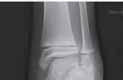

Podział złamań kości rosnących, tzw. złamań nasadowych: A – schematyczne przedstawienie klasyfikacji złamań; B – SH I (RTG, widok z przodu i z boku); C – SH II (RTG, widok z przodu i z boku); D – SH II (TK, widok z boku); E – SH III (RTG, widok z przodu i z boku); F – SH IV (RTG, widok z przodu i z boku); G – SH V (RTG, widok z przodu i z boku).

Rozpoznanie

Objawy złamania to silny ból uniemożliwiający stanie i chodzenie, zniekształcenie obrysów stawu kolanowego przez krwiak i różnego stopnia przemieszczenie nasady kości piszczelowej. Należy dokładnie zbadać stan ukrwienia i unaczynienia kończyny pod kątem objawów uszkodzenia tętnicy podkolanowej i nerwu strzałkowego. Trzeba ocenić bolesność uciskową oraz napięcie w przedziałach powięziowych podudzia: przednim, bocznym, tylnym powierzchownym i tylnym głębokim. U pacjentów z podejrzeniem wzmożonego ciśnienia wewnątrzprzedziałowego należy wielokrotnie powtarzać badanie ukrwienia i unerwienia kończyny, a w razie zaistnienia wskazań wykonać bezpośredni pomiar ciśnienia w przedziałach. Powinno się zawsze podejrzewać możliwość uszkodzeń więzadłowych współistniejących ze złamaniem. Badania obrazowe to RTG w pozycji AP, bocznej i skośnej. Wykonanie badania TK może być konieczne w celu pełnej oceny rozległości

złamania. W przypadku podejrzenia uszkodzenia tętnicy podkolanowej należy wykonać angio-TK lub arteriografię.